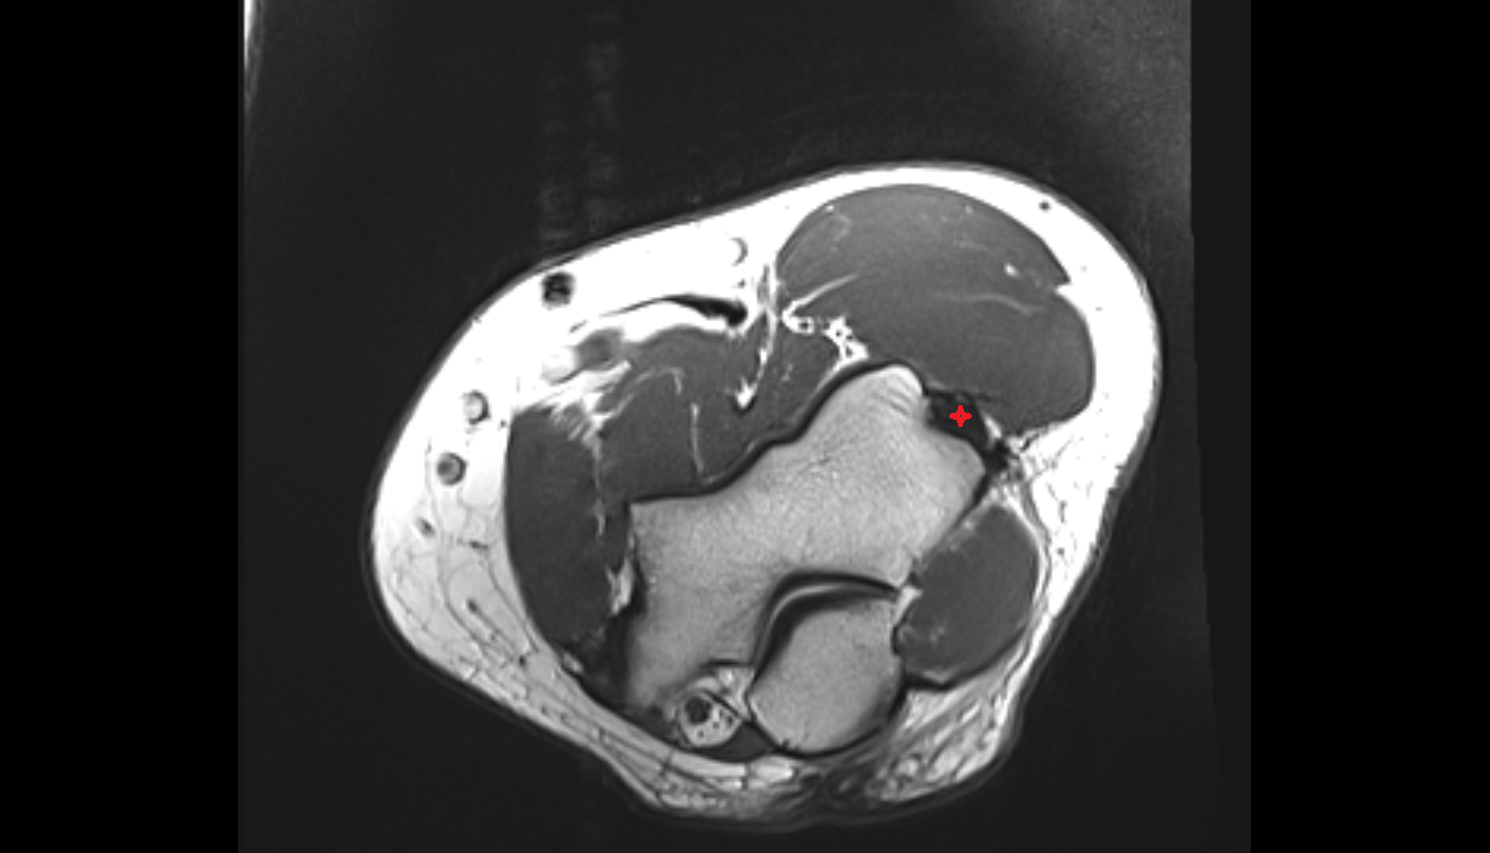

- Meniscus cartilage

- Medial meniscus

- Lateral meniscus

- Knee Joint